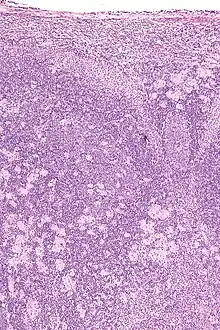

Lymph nodes affected by Toxoplasma have characteristic changes, including poorly demarcated reactive germinal centers, clusters of monocytoid B cells, and scattered epithelioid histiocytes.